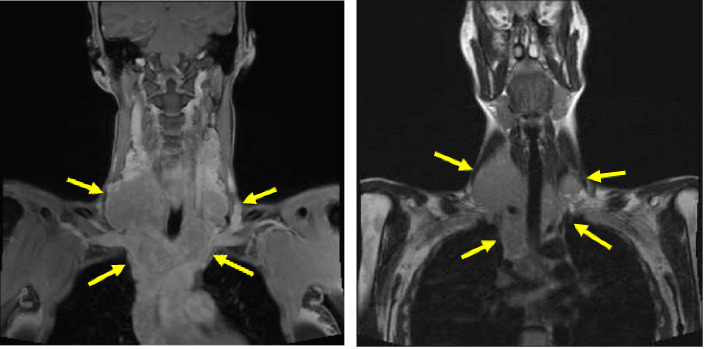

Hodgkin's lymphoma (HL) is uncommon, and its etiology has been attributed to infectious sources such as Epstein-Barr virus (EBV). Though pathogenesis is not completely understood, studies have revealed that specific viral proteins from EBV conduct the process of HL development. In this report, we will discuss the case of a patient who developed EBV-associated classic HL 15 years after an episode of infectious mononucleosis.